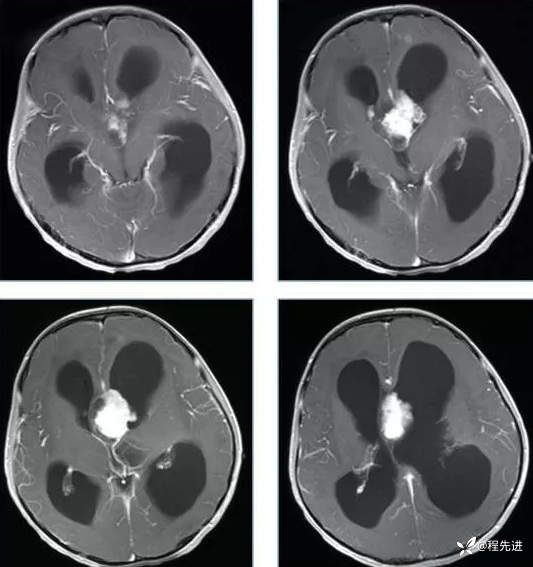

【神经】特别精彩病例|行走不稳2月余

患者性别:男

患者年龄:13岁

主诉:行走不稳2月余

现病史:2个月前患者无明显诱因下出现行走不稳,近期症状逐渐加重,站立不能。病程中患者无意识障碍,无头痛头晕,无明显恶心呕吐、视物旋转、耳鸣、眼球活动障碍等,无尿量增多、泌乳、口干等,体重无明显改变,睡眠可,食欲可,二便正常。

既往史:患者生后8个月和今年出现两次癫痫发作,持续时间不长

个人史:患者自幼失语,智力障碍

专科检查:右侧肢体肌力III-IV级,左侧肢体肌力IV级,肌张力下降